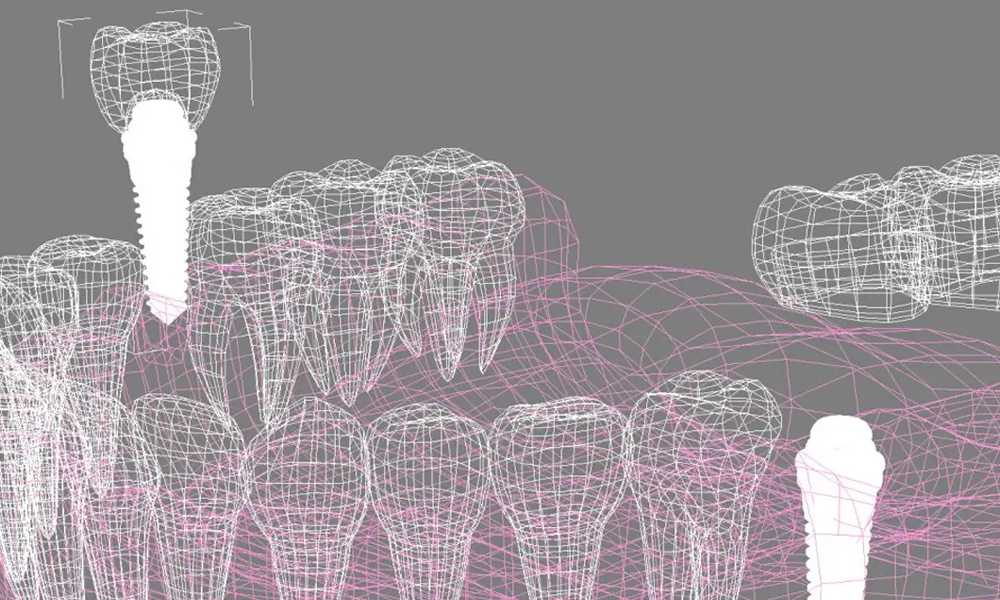

با استفاده از فناوری CAD/CAM، محل دقیق ایمپلنت و طراحی گاید جراحی انجام میشود. این مرحله بسته به پیچیدگی درمان ممکن است چند روز تا یک هفته طول بکشد. - جراحی و قرار دادن ایمپلنت

۴. طراحی دندانهای مجازی و موقعیت ایمپلنت

با استفاده از نرمافزارهای طراحی، دندانهای از دسترفته بهصورت مجازی در جای خود قرار میگیرند و موقعیت دقیق ایمپلنتها تعیین میشود تا روکش نهایی عملکرد طبیعی و زیبایی ظاهری داشته باشد.

۵. ساخت گاید جراحی سهبعدی